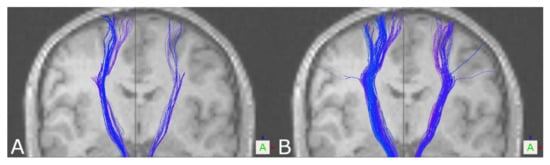

3.1. The Corticospinal Tract

3.2. The Optic Radiation